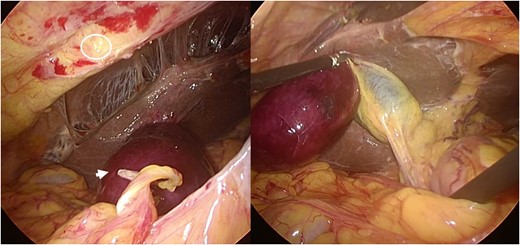

A computed tomography (CT) image revealed a gourd-shaped gallbladder with biphasic appearance divided clearly at the body. In the fundus side, the wall of the gallbladder was oedematous and thickened, while the neck side was intact (Fig. 1). The preoperative diagnosis was torsion of the gallbladder. After admission, her abdominal symptoms showed improvement, although they did not disappear completely. On the second day after onset, we planned to perform a laparoscopic cholecystectomy (LC). During laparoscopy, a tip of the omentum encircling the gallbladder was strangling the gallbladder and had adhered to the abdominal wall. By cutting the attachment site of the omentum, the strangulation was released and a whole image of the gallbladder appeared (Fig. 2). The gallbladder was found to have been strangulated by a tip of the omentum attached to the abdominal wall without torsion. The gallbladder was oedematous and congested, although it did not show apparent gangrenous change. We performed LC. The borderline between ischaemic change and non-ischaemic change in the specimen was apparent (Fig. 3).

Intraoperative laparoscopic finding. A tip of the omentum encircling the gallbladder adhered to the abdominal wall and strangled the gallbladder. By cutting the attachment site of the omentum, the strangulation was released and a whole image of gallbladder appeared. The gallbladder was found to have been strangulated by the band between the omentum and abdominal wall. A circle shows the attachment site of the omentum at the abdomen. The arrow shows the tips of the omentum, which encircled and strangled the gallbladder.